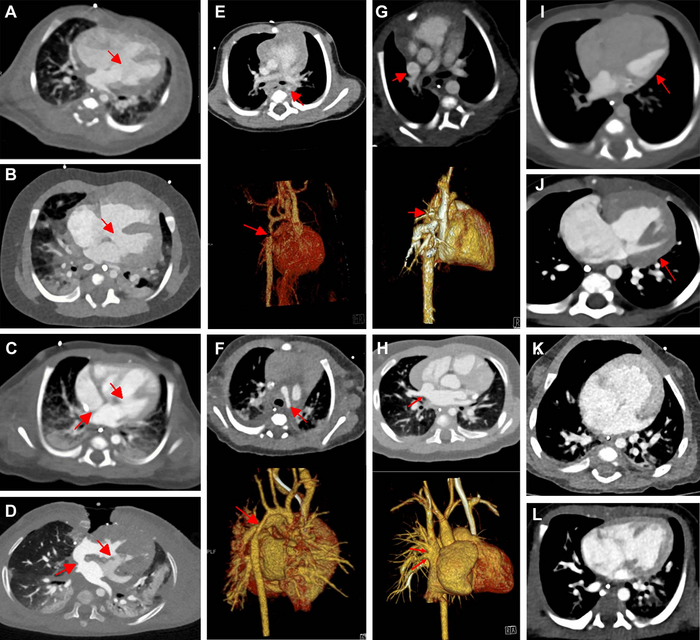

Contrast-enhanced axial dual-source CT (DSCT) versus contrast-enhanced axial photon-counting CT (PCCT) interindividual comparisons in typical congenital heart defects. (A) DSCT image in a 15-day-old male infant suspected at sonography of having ventricular septum defect (arrow). (B) PCCT image in a 155-day-old male infant suspected at sonography of having ventricular septum defect (arrow). (C) DSCT image in a 25-day-old male infant suspected at sonography of having atrioventricular septum defect (arrows). (D) PCCT image in a 355-day-old male infant suspected at sonography of having atrioventricular septum defect (arrows). (E) Contrast-enhanced and three-dimensional (3D) DSCT images in a 128-day-old male infant suspected at sonography of having aortic isthmus stenosis (arrows). (F) Contrast-enhanced and 3D PCCT images in a 16-day-old male infant suspected at sonography of having hypoplastic aortic arch (arrows). (G) Contrast-enhanced and 3D DSCT images in a 63-day-old male infant suspected at sonography of having partial anomalous pulmonary venous connection (arrows). (H) Contrast-enhanced and 3D PCCT images in a 174-day-old male infant suspected at sonography of having partial anomalous pulmonary venous connection (arrows). (I) DSCT image in a 2-day-old male newborn with hypoplastic left heart syndrome (arrow). (J) PCCT image in a 149-day-old male infant with hypoplastic left heart syndrome (arrow). (K) DSCT image in a 10-day-old male newborn with double outlet right ventricle. (L) PCCT image in a 7-day-old female newborn with double outlet right ventricle.